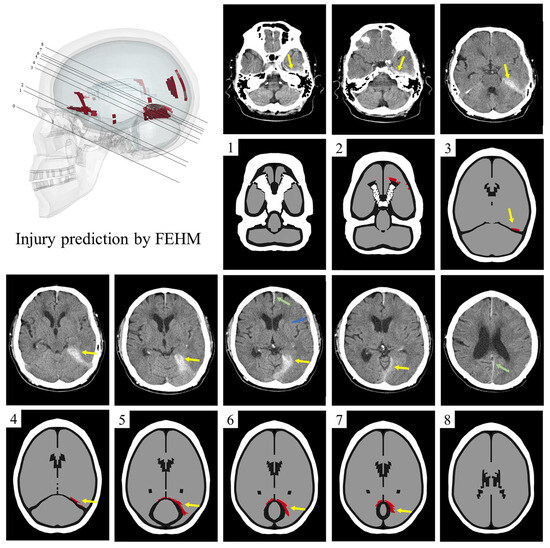

3.2. Injured Areas in FEHM and CT Images

3.3. Injured Predictions in Occipital Impacts